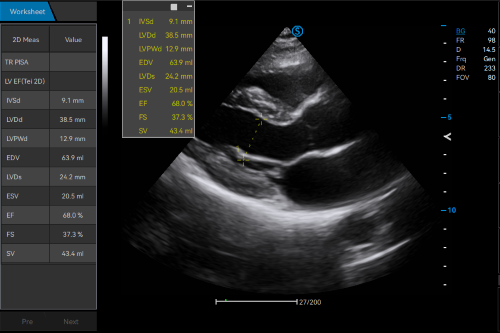

Intelligent Breast Solutions on the Workstation

Automatic lesion detection powered by AI identifies suspected area and traces the lesion from multiple sections. Quantitative coordinate position and graphic indication will be displayed for precise lesion localization.

Lesion stereo images are generated from volume data rendering. It provides intuitive and detailed information for better observation and lesion localization.

Auto OB automatically measures the common fetal biometric results (HC, BPD, FL, etc.) in standard sections.

Auto NT automatically recognizes and measures the thickness of the fetal nuchal translucency.

Lumi 4D enables the adjustment of light source angle to support real-time static stereo imaging of the fetus.